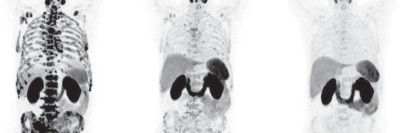

Verdächtige Halslymphknoten mit "PSMA-radio-guided surgery" aufspüren

Ein Patient mit Verdacht auf zervikale Metastasen eines bereits bekannten Prostatakarzinoms stellt sich vor. Im Tumorboard wird beschlossen eine „PSMA-radio-guided surgery“ durchzuführen. Die moderne Technik, um Prostatakarzinommetastasen intraoperativ zu identifizieren, wurde bisher bei abdominellen und pelvinen Lymphknotenmetastasen angewandt. Der Fall zeigt, dass die Methode auch bei Halslymphknotenmetastasen umsetzbar ist.

Einem Mann wird Blut abgenommen/© auremar / stock.adobe.com (Symbolbild mit Fotomodellen), Jüngere Hand hält ältere Hand/© Joel bubble ben / stock.adobe.com (Symbolbild mit Fotomodellen), Radionuklidtherapie bei einem Patienten mit metastasierten kastrationsresistenten Prostatakarzinom /© Willner L et al. / all rights reserved Springer Medizin Verlag GmbH, Koloskopie/© Kzenon / stock.adobe.com (Symbolbild mit Fotomodellen), Infusionstropf im Krankenhaus /© Trsakaoe / stock.adobe.com, Blut wird abgenommen/© geargodz / stock.adobe.com (Symbolbild mit Fotomodellen), Ga-PSMA-PET MRT Verdacht auf Prostatakarzinom/© Springer Medizin Verlag GmbH, Typisches Beispiel eines intraduktalen Karzinoms der Prostata./© Kristiansen, G. et al. / all rights reserved Springer Medizin Verlag GmbH, Mann nimmt eine Tablette ein/© Jelena Stanojkovic / stock.adobe.com (Symbolbild mit Fotomodell), Blutproben im Labor/© PeopleImages / Getty Images / iStock, Urologe erklärt Patienten urologischen Eingriff an einem Modell /© Witoon / Stock.adobe.com (Symbolbild mit Fotomodell), Muzinöses Prostatakarzinom/© Garzaro JRR et al. / all rights reserved Springer Medizin Verlag GmbH, Hypertrophe, teils pseudopolypös anmutende Schleimhautfalten, mit Koagel, Sickerblutung und Hämatin/© H. Lutz, PSMA-spezifische Traceranreicherung zweier Lymphknoten tief linkszervikal/© Lingl, J.P., Böhm, F., Wiegel, T. et al., Ein Mann erhält eine Infusion/© Denis / Stock.adobe.com (Symbolbild mit Fotomodell), Search Icon, Teaserbild Blutungsrisko managen bei Antikoagulation - Waage/© Leo Pharma GmbH, Vortrag Frankfurter Gerinnungssymposium/© LEO Pharma GmbH (Screenshot aus Vortrag), 3 Empfehlungen für niereninsuffiziente Patienten/© LEO Pharma GmbH, Thrombus und Patientin im Gespräch/© crevis / adobe.stock.com (Symbolbild mit Fotomodell)